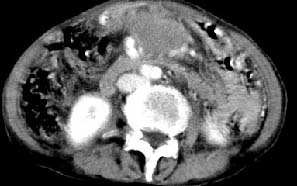

肝胃之间、肝十二指肠韧带,胰头后、腹主a周围,融合而成团块状影,包绕血管[腹腔干、肠系膜上动脉,腹主动脉],胰腺前移后缘分界欠清,与肝胃分界清,肿块未见明显强化,肝右叶后段小囊肿。

主动脉-胰腺间隙可见巨大分叶状软组织肿块影,包绕腹主动脉、腹腔干及其分支、腔静脉等大血管,增强呈无明显强化,临近脏器明显受压移位,增强示有分界。肝右叶可见局限性低密影,边缘清楚。

考虑腹膜后淋巴瘤。

再看从肠系膜根部到胰腺后主动脉及上腔静脉周围可见相连的较大的软组织肿块影,形态不规则,呈明显

的大小不等的分叶状,其中密度较均匀但其中可见条状低密度区,肿块边缘比较清晰周围的小肠受压移位

明显且堆积。

增强所见,腹腔动脉,肠系膜上动静脉被肿块包绕,结合平扫的条状低密度区恰好位于血管周围,较大的

肿块强化不明显(遗憾的是没有标上ct值)但胃壁强化的十分明显。

影象诊断:考虑淋巴瘤待除外胃癌腹膜后淋巴结转移

讨论:首先看肠系膜和腹膜后的肿块我认为是多发融合的肿大的淋巴结。理由1大小不等的分叶,分布比较

自由。2其中的包绕的血管和周围少量的脂肪即所说的。

同时胃的影象表现和临床的不典型表现,所以我认为淋巴瘤,临床表现不支持胃癌